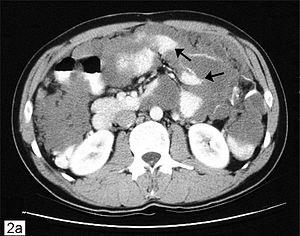

Computed tomographic scan of an abdomen showing pseudomyxoma peritonei with multiple peritoneal masses (arrow) with "scalloping effect" seen.